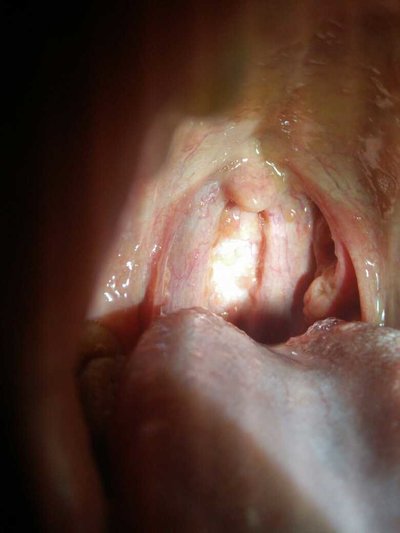

Almost all squamous cell carcinoma of the soft palate occurred on the oral surface of the soft palate (below). There was almost no tumor on the nasopharynx. Even the larger tumors in the nasopharynx rarely invaded the soft palate and nasopharynx. In the early stage, the tumor was red and the boundary was not obvious. White lesions of soft palate are also common, which may be leukoplakia, carcinoma in situ or early invasive carcinoma. Multiple tumor growth on the surface of normal mucosa is a common feature. Most soft palate cancers are limited to the soft palate or the adjacent tonsillar arch. The T grade is T2 or T3, but the tumor volume is smaller than that of the tongue base and tonsillar fossa. In the middle and advanced stage of cancer, there are ulcers, marginal protuberances, or exogenous growth, especially around the uvula. Soft palate tumors first spread to tonsil arch and hard palate.